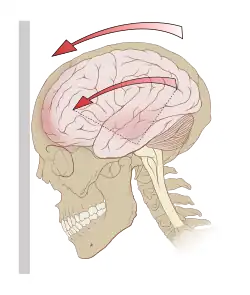

Siły działające na mózg w trakcie urazu mogące doprowadzić do wstrząśnienia | |

Wstrząśnienie mózgu (łac. commotio cerebri) – zaburzenie czynności pnia mózgu, będące wynikiem urazu lub zniesienia czynności komórek zwojowych mózgu bez znaczących zmian anatomicznych. Uznawane jest za łagodną postać urazowego uszkodzenia mózgu[1].

Utrata przytomności we wstrząśnieniu mózgu jest spowodowana zaburzeniem funkcji tworu siatkowatego na skutek ruchu obrotowego, który działa na górną część pnia mózgu[2].